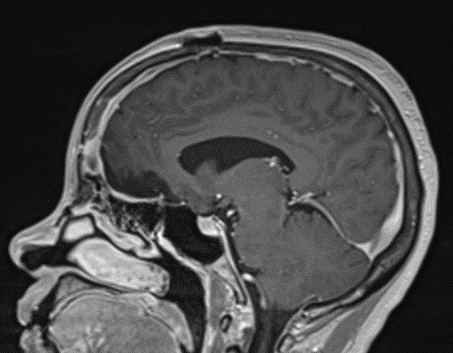

Figure 2a – Preoperative MRI demonstrating an extra-axial lesion with surrounding vasogenic edema and mass effect on the frontal lobes.

Figure 2b – Postoperative MRI demonstrating resolution of mass effect.